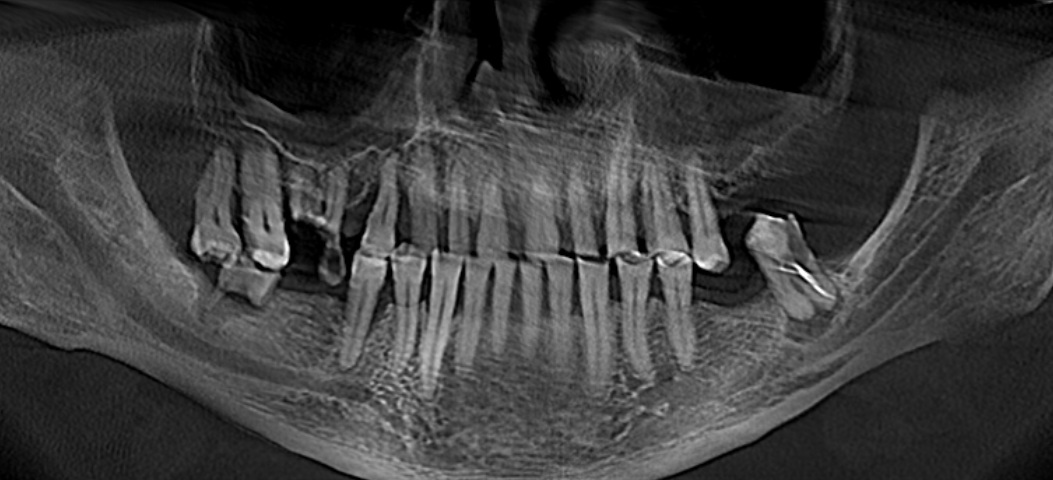

Я подготовился к приему заранее, посмотрел компьютерную томографию, которую он мне прислал.

По снимку видно, что необходим комплексных подход к проблеме, который будет включать в себя мою работу, как хирурга, так и смежных специалистов. Гигиениста, ортопеда и терапевта.